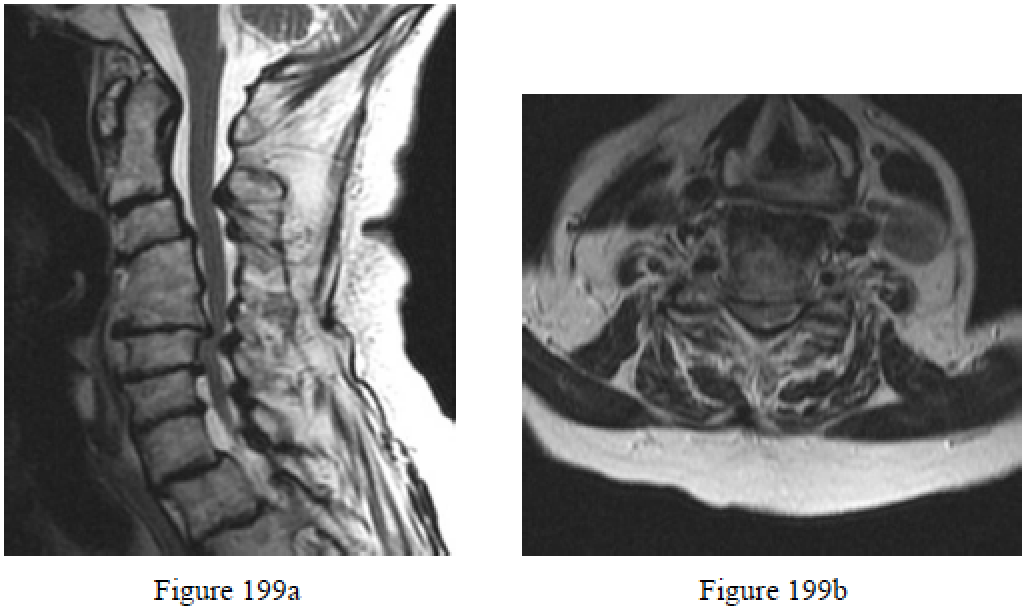

Question 199

Figures 199a and 199b are the sagittal and axial T2-weighted MR images of a 76-year-old woman who has been experiencing worsening coordination and gait imbalance during the past year. When compared to an anterior surgical approach, a posterior approach is associated with a significantly higher indicence of which perioperative complication?